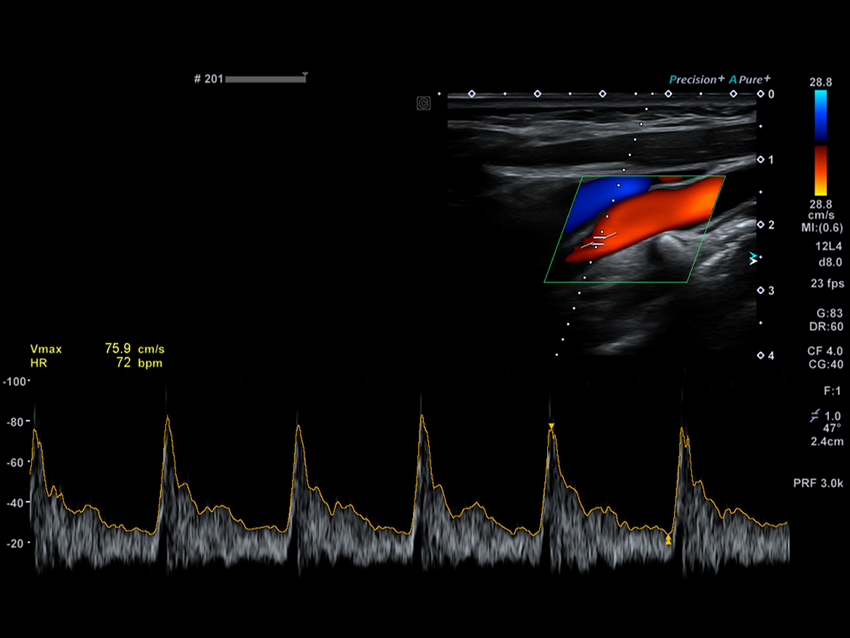

Автоматичне допплерівське стеження спрощує робочий процес за допомогою імпульсно-хвильових допплерівських (PWD) вимірювань.

Автоматичне вимірювання комплексу інтима-медіа  Auto IMT допомагає підвищити як точність, так і швидкість допплерівських досліджень сонної артерії.